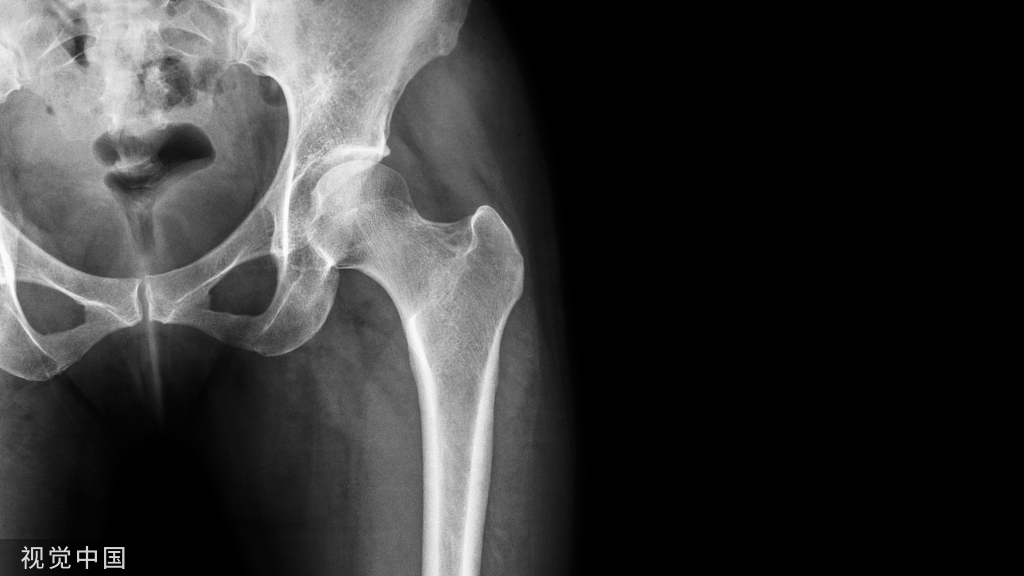

术前X线片:股骨远端骨不连,接骨板疲劳折断

折断接骨板微创取出的手术过程。

技术要点股骨髁骨板,重点在髁部,故髁部切口较长,利用该切口取出远端螺钉及折断的远端接骨板;通过克氏针的引导,于近端复加数个小切口经皮取出相应的螺钉,于远端切口取出折断的近端接骨板。